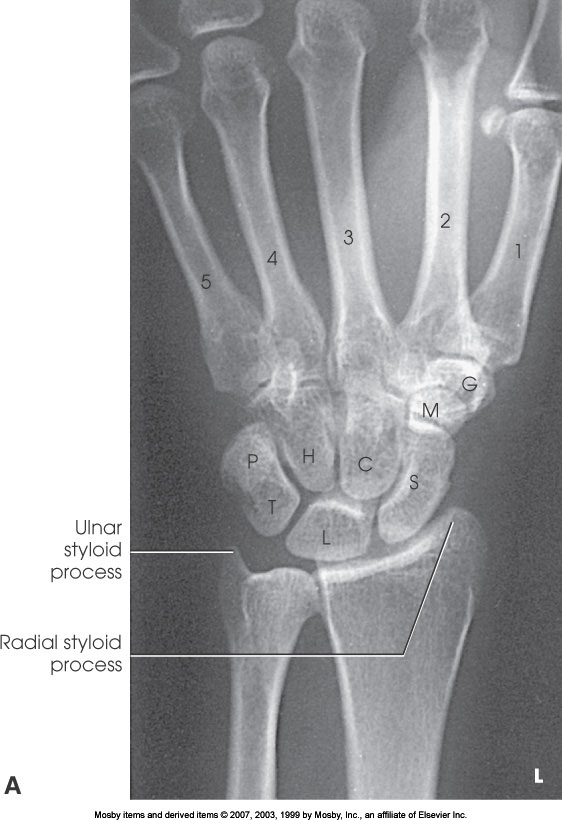

What position is demonstrated?

PA Wrist